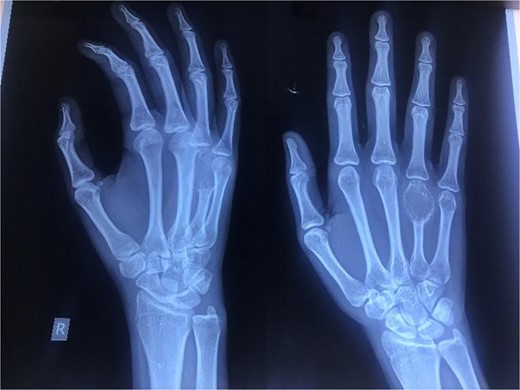

A 20-year-old female, with an unremarkable past medical and surgical history, presented to our clinic with a progressively increasing, painful swelling on the right-hand dorsum on the fourth distal MCP region (Fig. 1). Local examination revealed a 3×3 cm solid immobile swelling at the distal fourth MCP which was painful upon complete extension and flexion. A plain radiograph (Fig. 2 arrow) showed the hallmark expansile soap bubble lesion involving the entire distal fourth MCPJ approaching the articular surface of the MCP. The patient’s routine lab workup was unremarkable. She was counseled regarding all options to make an informed decision and opted for a wide local excision of the lesion along with reconstruction using a free MTPJ transfer.

Oblique (left) and antero-posterior (right) view of the right hand revealing an expansile, lytic lesion with a soap bubble appearance over the entire fourth metacarpal bone with thinning of the cortex.